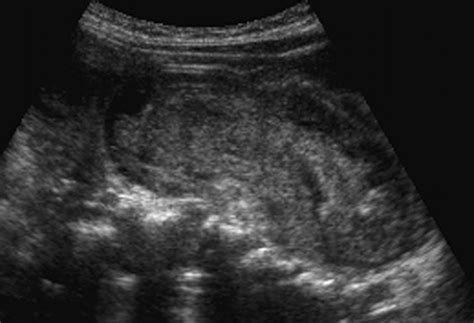

Ultrasound is a valuable tool for diagnosing intussusception, especially in pediatric patients. It provides real-time imaging and can detect the characteristic “target” or “doughnut” sign, which indicates the presence of intussusception. The ultrasound probe is placed on the abdomen, and the radiologist looks for the following signs:

• Pseudo-Kidney Sign: An elongated, oval structure resembling a kidney, seen in longitudinal sections.